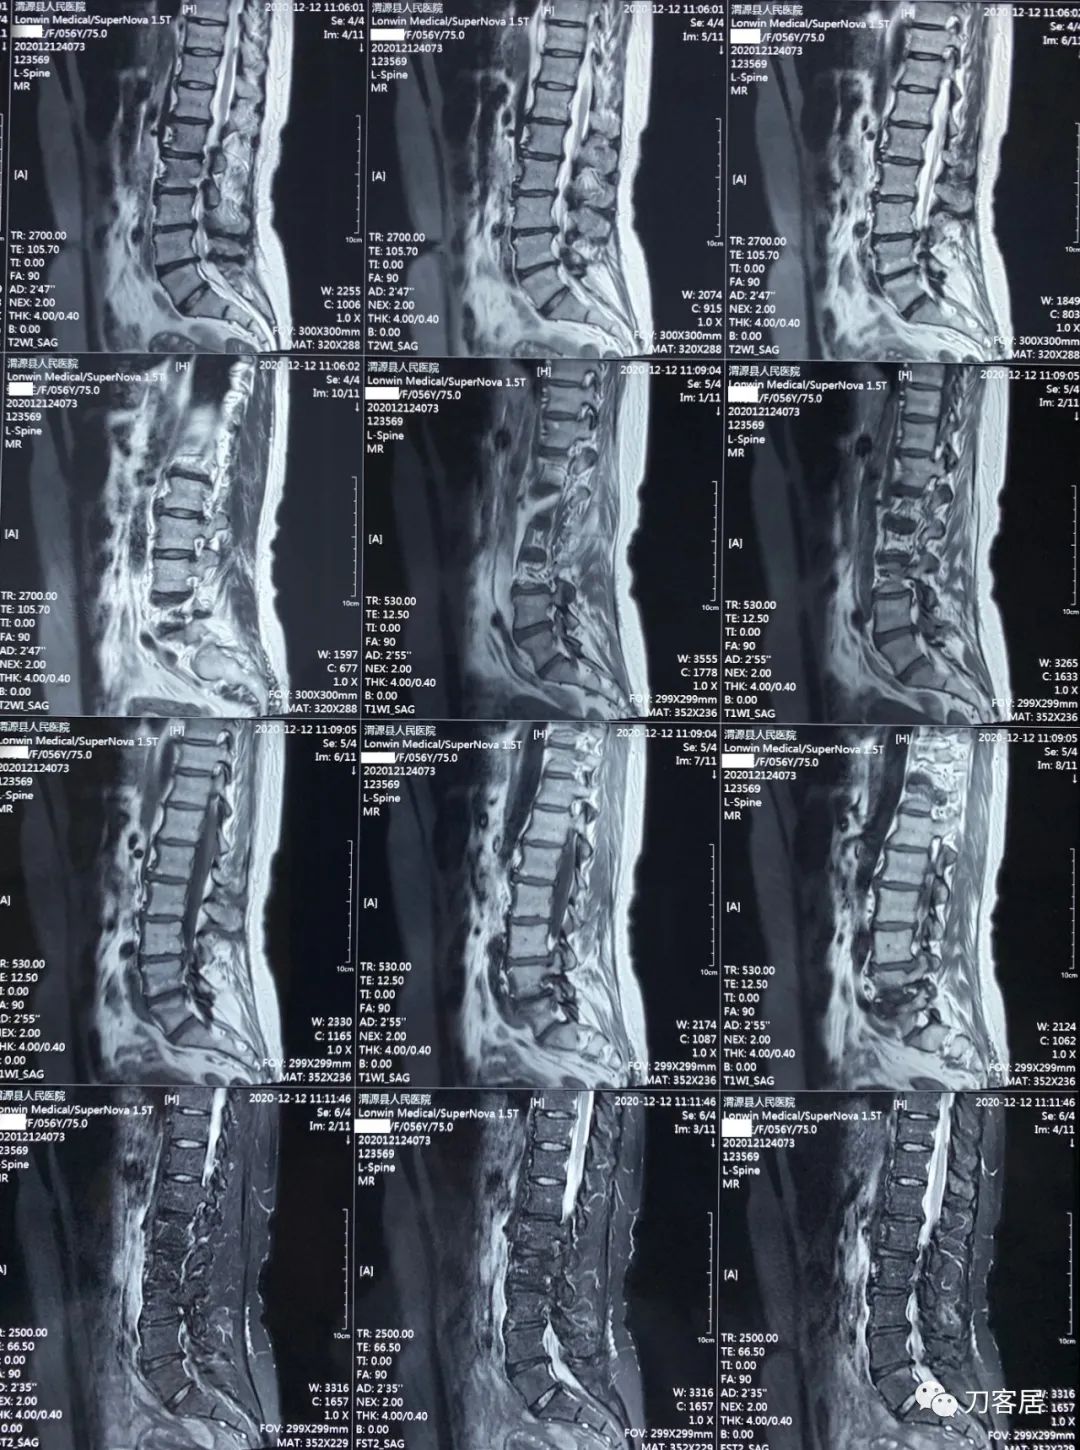

2021年12月12日去渭源县医院做颈椎腰椎MRI,提示1.腰椎侧弯畸形并骨质增生,2. L5S1椎体终板炎(I型), 3. L1-S1椎间盘变性并腰2-4,腰5骶1椎间盘膨出,腰4-5椎间盘突出并相应平面继发性椎管狭窄。2020年12月中旬于渭源县医院行骶管注射2次6针后睡眠改善,

2021年5月17日,西京医院骨科门诊找我就诊,自带影像学检查资料提示腰椎侧弯,腰3-4,腰4-5椎间盘突出,黄韧带肥厚,椎管狭窄。

从这个患者的影像资料分析,颈椎间盘突出问题不大,没有明确的上位神经元损伤表现,所以,不考虑颈椎和胸椎问题。腰椎侧弯畸形,但不严重。因为存在腰椎侧弯,使得腰椎MRI在扫描切面的时候,显示的椎间盘突出或椎管狭窄会有一定的误差,所以,又加做了经椎间盘的CT平扫,影像表现并不严重,综上,腰椎间盘突出,腰椎管狭窄,腰椎侧弯,不考虑手术治疗。同时,患者的主要痛苦是心理疾病,而不是器质性疾病,所以,以心身疾病治疗为主。虽然患者骨密度检查结果提示正常,但X线片显示骨质疏松,且其症状也与骨质疏松的症状有符合之处,比如静息痛,不能入睡,动作及姿势变换时痛加重等,所以,给予实验性抗骨质疏松治疗,以观疗效。